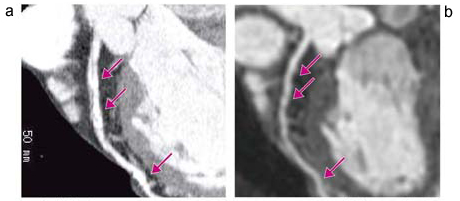

図2 80歳,女性(胸痛)

a:本症例でも,MDCTではLADの近位,中間部に高度石灰化(↓)があり,狭窄病変の評価ができなかった。

b:MRCAでは,同部分は石灰化の影響を受けずに描出されており(↓),高度な狭窄がないことが判明した。